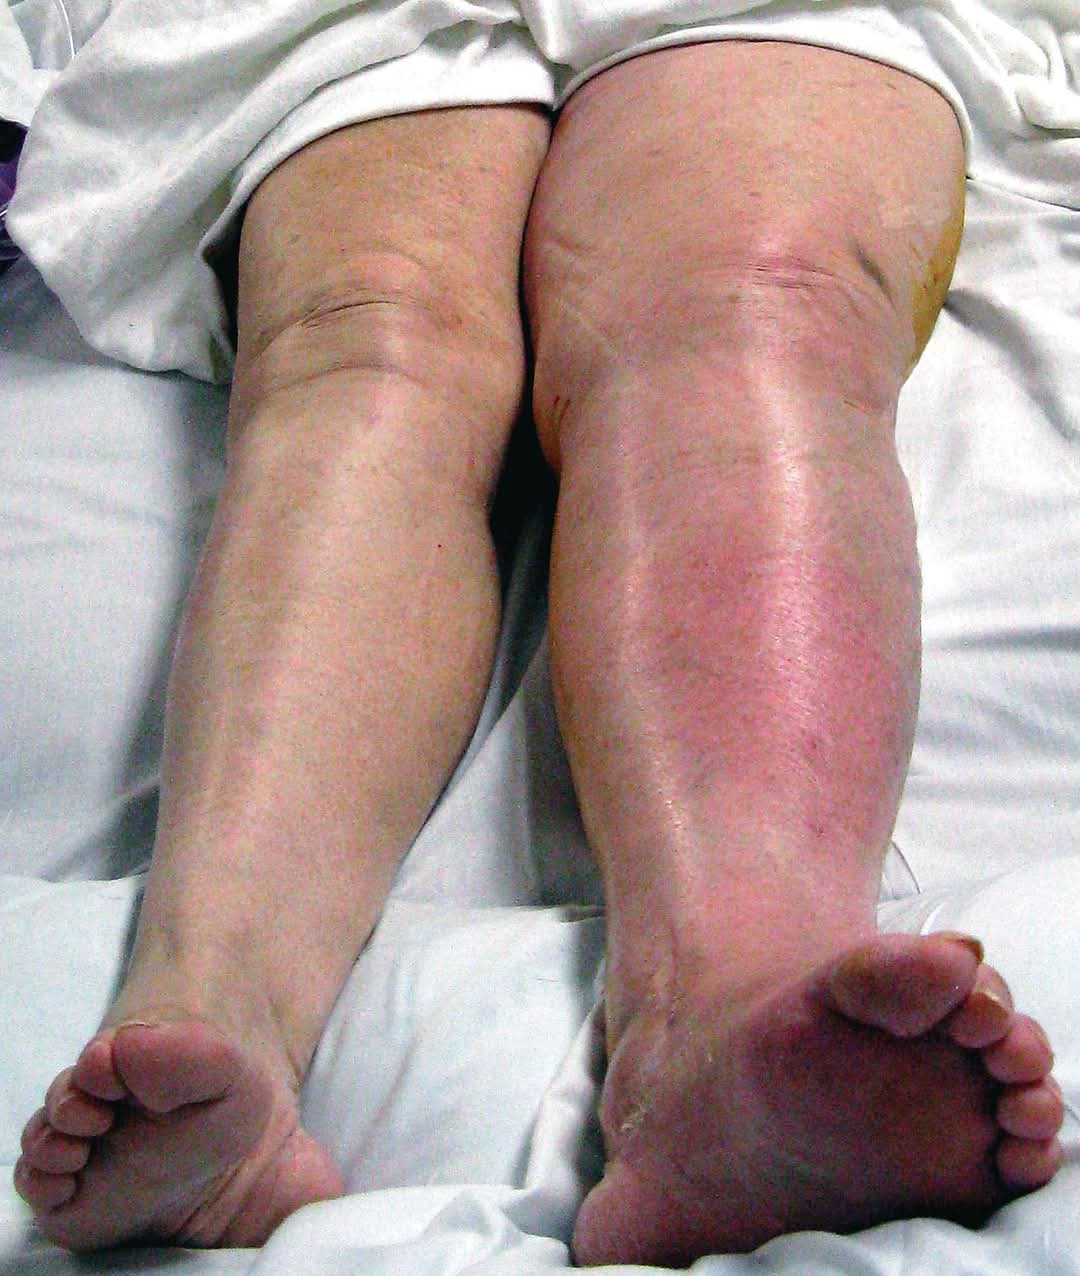

หน้าหลัก > ความรู้ทั่วไป ความรู้ทั่วไป 16 พ.ย. 2568 เลือดจาง” ไม่ใช่แค่ซีด — แต่มันคือภาวะที่ร่างกายขาดออกซิเจนเรื้อรัง 29 ต.ค. 2568 นี่คือสภาพใยประสาทในสมองคุณที่เต็มไปด้วย ‘ขยะพิษ’ (β-amyloid) 31 ส.ค. 2568 "การตรวจที่จำเป็นและเหมาะสม" เป็นสิ่งที่เพียงพอแล้ว 21 ส.ค. 2568 3 สิ่งง่ายๆ ที่ช่วยลดความเสี่ยงมะเร็ง 19 มิ.ย. 2568 📌 สรุปวิธีสร้างฮอร์โมนไทรอยด์ กว่าจะได้ ไม่ได้ง่ายๆ นะเออ 17 มิ.ย. 2568 เมื่อประมาณ 42,000 ปีก่อน มีสิ่งผิดปกติเกิดขึ้นกับ สนามแม่เหล็กโลก 5 มิ.ย. 2568 ⚠️ ขาบวมแดงข้างเดียวแบบนี้ เกิดได้จากหลายโรค อย่าปล่อยไว้ โดยเฉพาะโรคแรก เสียชีวิตได้ 14 พ.ค. 2568 อ้วน คือ 1 ในสาเหตุที่ทำให้นอนกรน 28 เม.ย. 2568 4 วูบ สถานการณ์ต่างๆ เกิดจากกลไกใดบ้าง มาดูกัน 25 เม.ย. 2568 “หมอประชา” ไขข้อสงสัย ร้อนจัดดื่มน้ำเย็นๆ ทำเส้นเลือดสมองแตกจริงไหม? 20 เม.ย. 2568 อย่า …ขู่ให้ลูกหยุดร้องไห้ …. 30 มี.ค. 2568 1